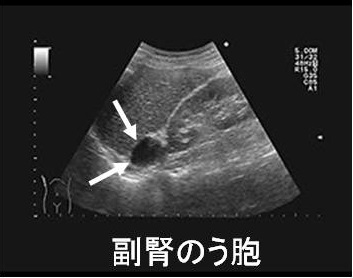

副腎嚢胞(副腎のう胞)は稀で、腹部超音波(エコー)検査の際に偶然見つかります。ほとんどが良性、無症状で、穿刺排液した後は経過観察になることが多い。

巨大な副腎嚢胞(副腎のう胞)は破裂の危険があるため手術適応になります[J Pak Med Assoc. 2023 Jun;73(6):1317-1319.]。